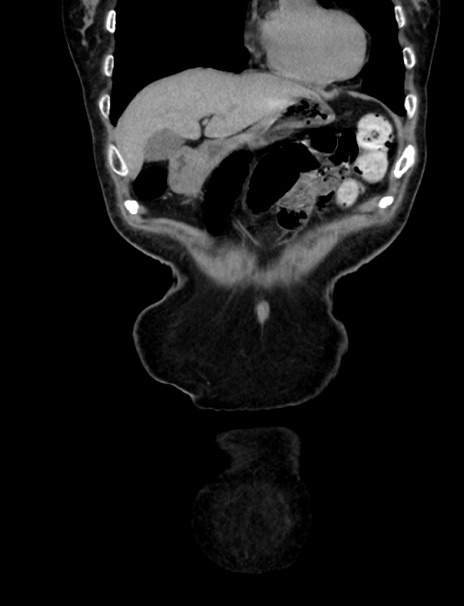

症例33(冠状断像)

【症例】70歳代 女性

【主訴】心窩部痛

【現病歴】延髄病変の精査・加療にて神経内科入院中。本日より心窩部痛あり。

【身体所見】右下腹部を中心に圧痛と反跳痛あり。

【データ】WBC 10900、CRP 0.02